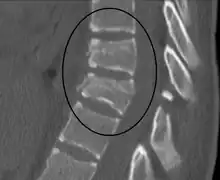

A Chance fracture of T10 and fracture of T9 due to a seatbelt during an MVC.

A flexion-distraction fracture of T10 and fracture of T9 due to a seatbelt during an MVC.